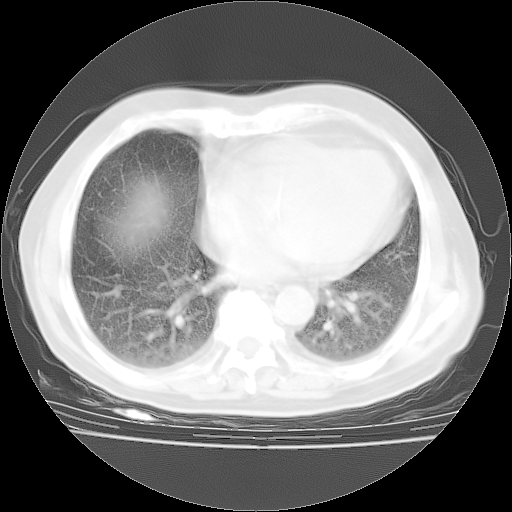

4月28日肺部CT——再次出现类似去年5月9日——透光度降低,“间质性”改变。

个人阅读4.14日肺部CT平扫:纵隔窗无异常,但肺窗示:双下肺内、后基底段有片絮状侵润影,部位以后基底段为著,以间质改变为主,呈急性肺泡炎征像,和首次住院影像学有相似之处。仅是个人读片,明日请相关专家再读片哈。其它建议同上。